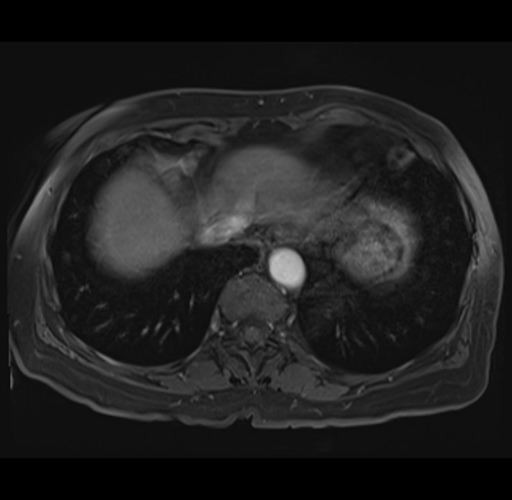

MRI T1

Imaging analysis

Based on your CT findings, which issue(s) would give reason for "planned slowing down moment(s)" in this case?

Considering a standard right hepatectomy procedure, what step(s) of the operation would you do differently in this case?